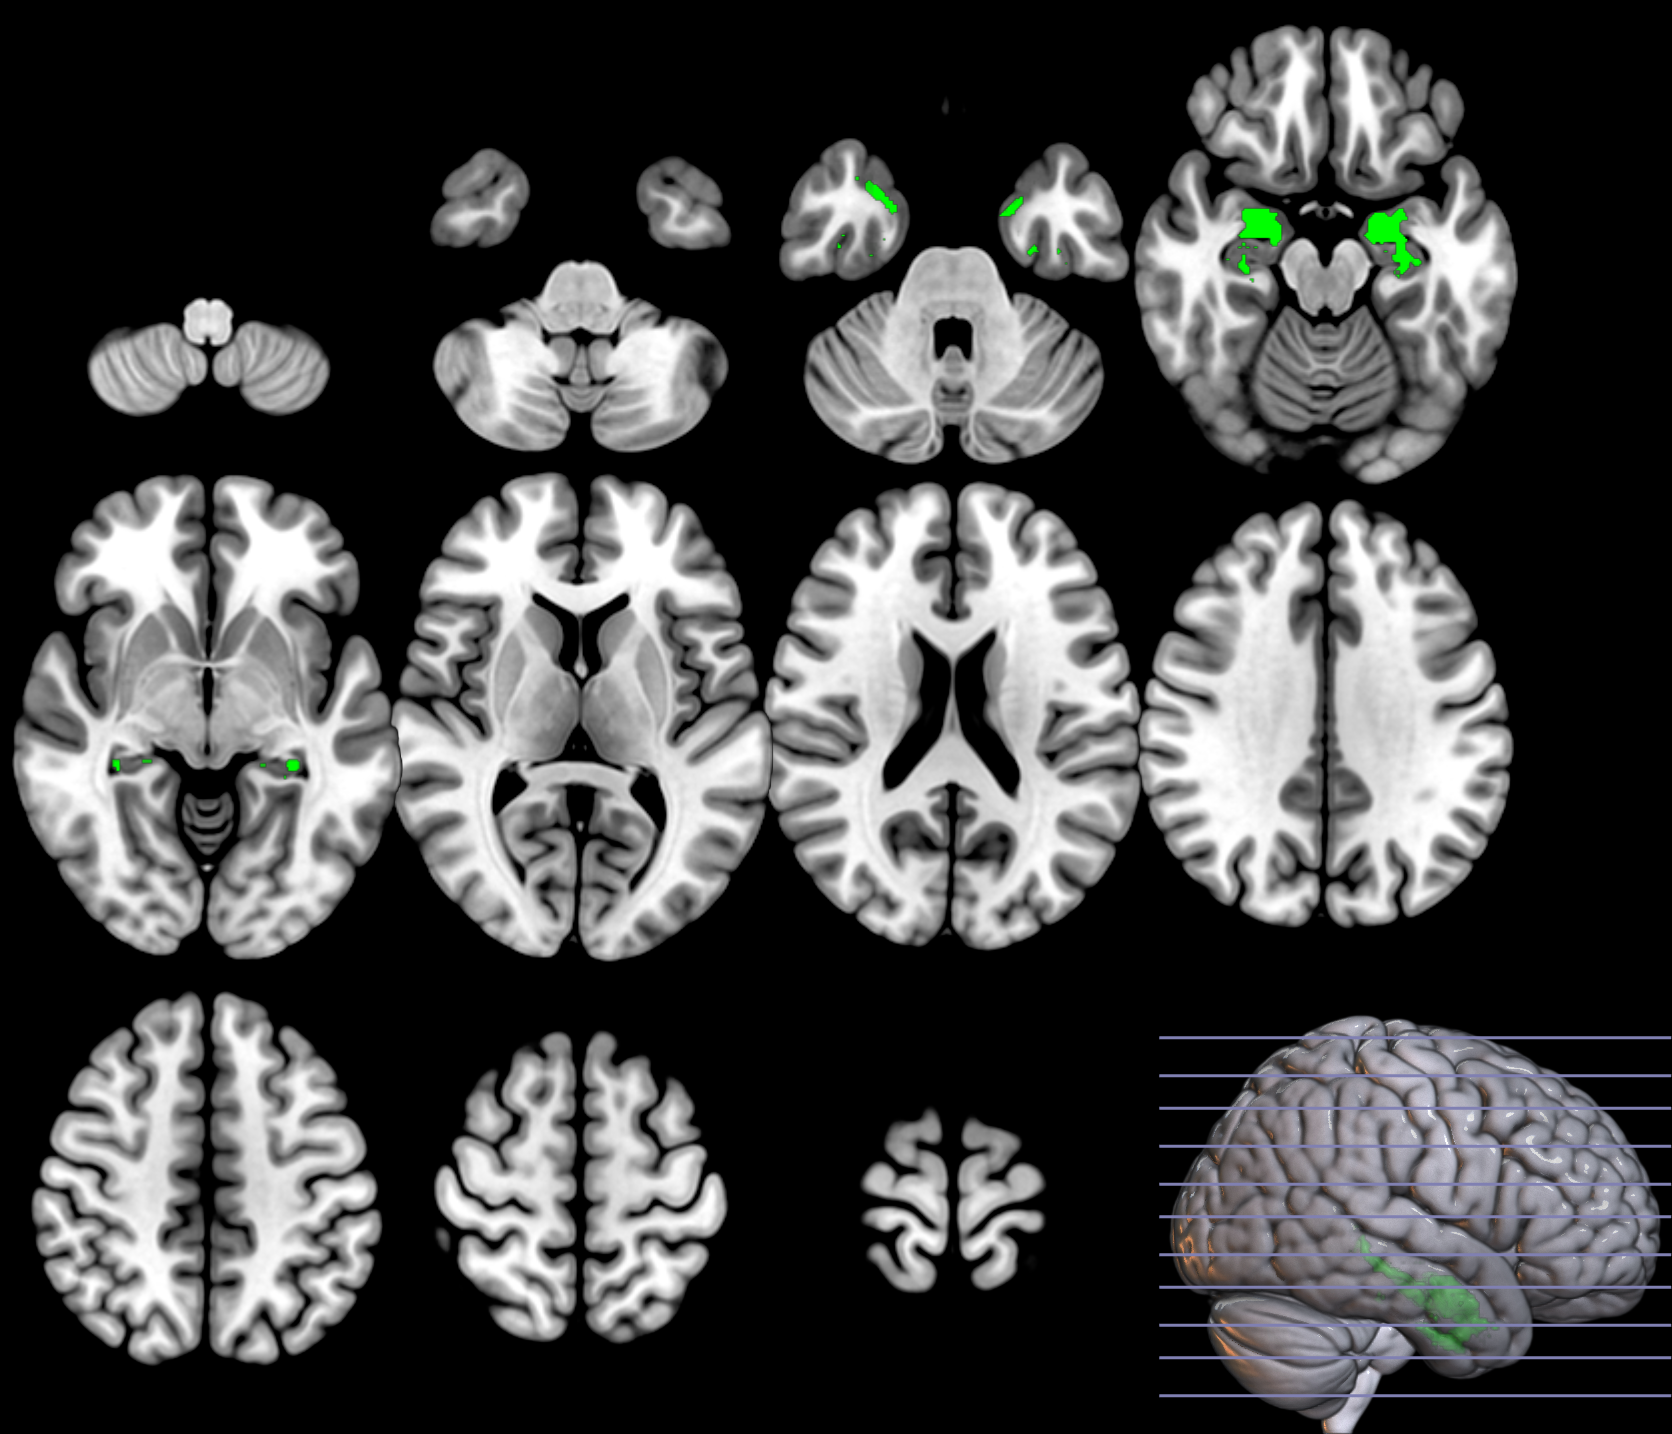

Based on the and values from the original dataset, and the ones obtained using a permutation analysis () for a selection of structures, e.g. hippocampus, we can compare the SPM with the previous inference approaches, as described in section 2.2.3. Note that in this paper the huge amount of voxels contained within an image limits the permutation analysis in this sense to some specific structures. Results on the hipocampus are depicted in figure 13. The permutation analysis reveals how the power of the approach is affected in this featured region, where a real effect might be found in almost the whole structure. The statistical power of the is preserved through the permutation procedure ( detected voxels vs voxels as shown in the same figure). It is also worth mentioning the CDF of the errors derived in the specific region and the distribution of the p-values within it. Recall that the dataset include advanced AD subjects thus the selected structure should be clearly affected by the disease.

To preliminary extend the analysis to the whole volume we approximately simulate the null distribution outside this featured region in two steps. First, we compute the set of p-values in the hippocampus (around voxels) following equation 16 and determine the T threshold that approximately provides the significance level, e.g. . Then, assuming that for any the probability of observation is , we threshold the rest of the image to obtain the significant voxels showing an effect. This approach clearly needs the multiple-comparison correction as several dependent or independent statistical tests are being performed simultaneously at the given significance level. Therefore, we decrease the significance level down to to avoid the presence of false positives in permutation analyses and then compare with SPM in the whole volume using the aforementioned configurations. In figure 13 we show the detection ability together with the control of type I error in the approach (map in red font). Note how the permutation test affects the detection ability of the classical CV approach (map in green font) and how the uncorrected voxelwise SPM approaches (in blue font ) tends to inflate false positives.